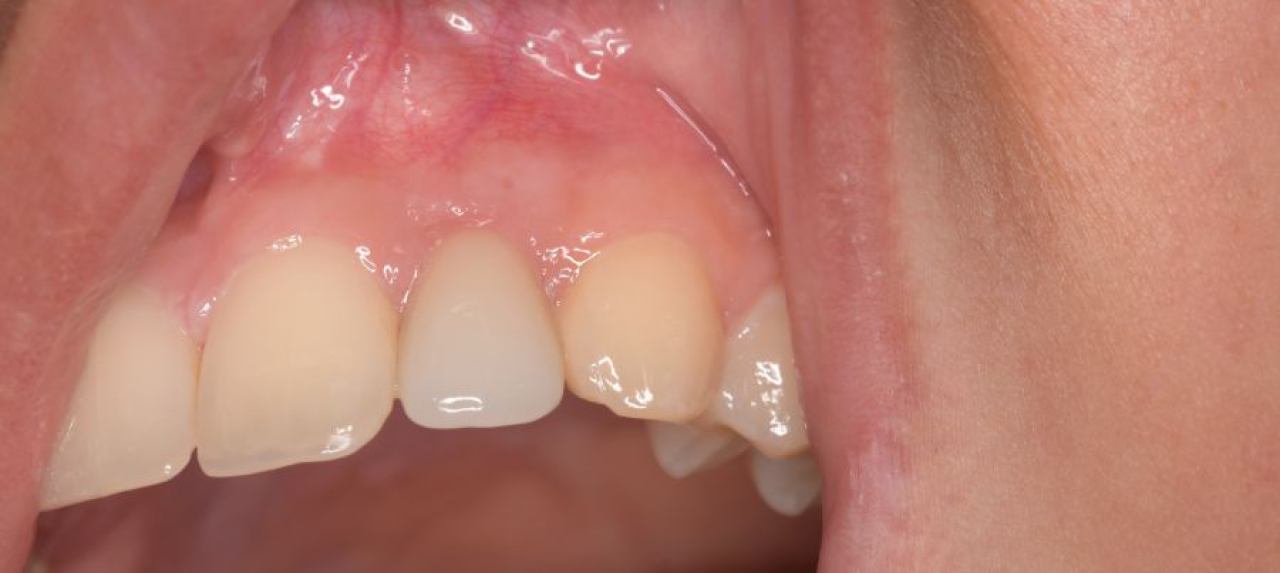

Regeneracija kosti i mekog tkiva

Gingivalne recesije u narodu poznatije kao „povlačenje zubnog mesa" moguće je korigirati kirurškim zahvatom te vratiti gingivu (zubno meso) u fiziološki položaj mikrokirurškim tehnikama. Zahvati koje odrađujemo kod regeneracije kosti i mekog tkiva su podizanje dna sinusa (sinus lift) i nadomještanje izgubljenog volumena kosti (augmentacija kosti, regeneracija kosti).